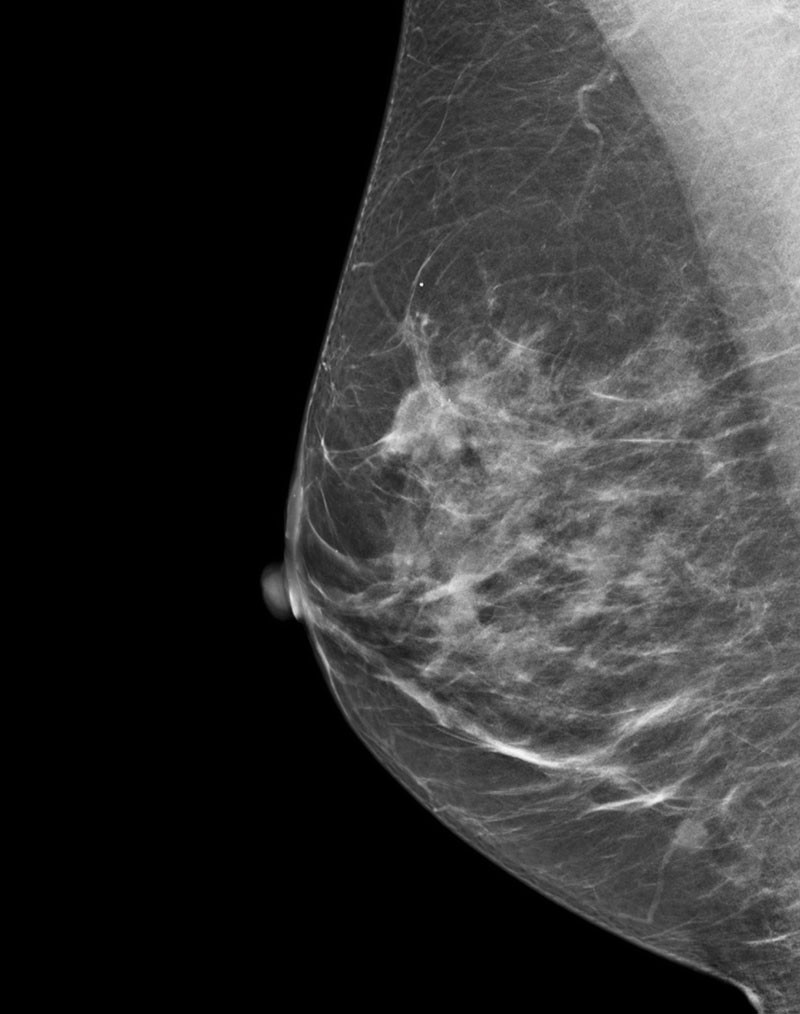

What are the fundamental principles of digital tomosynthesis?

The Fundamental Principles of Digital Radiographic Tomosynthesis interest, barrier-object distance, and radiation dose. The total dose ent reconstruction methods that have been developed. Originally, jection used with CT. Ho wever, this lead to signicant blurring and to the revolutions that occur in CT. Therefore the same principles

Digital tomosynthesis uses l - in conventional digital radiography. Additionally, noise is depen- vide insight into the depth of structures. With a larg er sweep angle, advanced optional application. GE, Shimadzu TM and Fujilm of - spectively.

What are the features of the GE senoclaire tomosynthesis system?

• Objective: To assess the degree and source of artifacts and to assure that the Flat Field image is Uniform. • 2D Acquisition in Mo/Mo, Mo/Rh, and Rh/Rh modes. • Review Raw Images from Browser • There is a separate Gain Calibration for the MTD to create uniform images.

How big is a GE senoclaire tomosynthesis paddle?

• 3 Available Paddles • 24 x 31, Elevated 24 x 31, Sliding 19 x 23 • 9 images acquired over a 250sweep. • Step and Shoot Acquisition • 100 micron pixel size ‐no binning of pixels • 5:1 Anti‐Scatter grid • MTD attachment weighs over 12 kg and is not counterbalanced ‐use caution if manually moving.